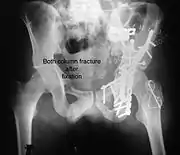

Posterior wall fracture fixed with screws and plate

The final management depends on the size of the fragment(s), stability and congruence of the joint. In some cases traction for six to eight weeks may be the only treatment required; however, surgical fixation using screw(s) and plate(s) may be required if the injury is more complex. The latter treatment will be called for if bone fragments do not fall into place, or if they are found in the joint, or if the joint itself is unstable.